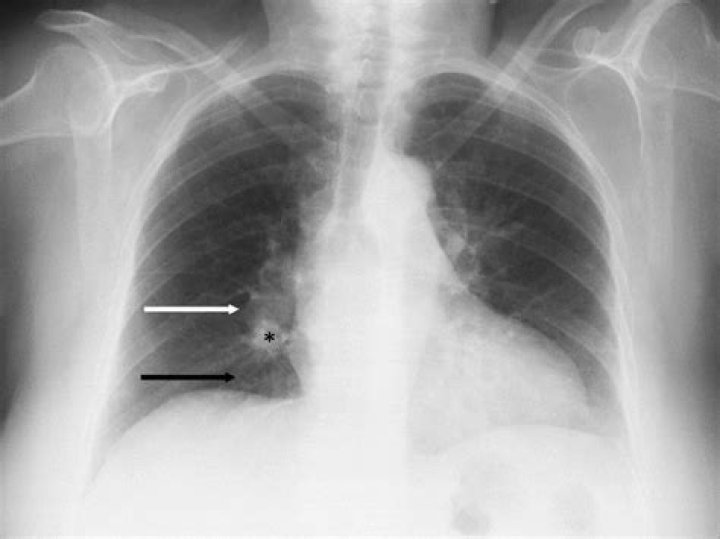

Esophageal cancer may not show symptoms in its early stages and is most often found in men over the age of 50. Your doctor may perform a physical exam, chest x-ray, chest CT, Upper GI x-ray, esophagoscopy, endoscopic ultrasound, or PET/CT to help determine if you have cancer and if it has spread.

The X-rays can highlight any abnormal areas in the inner lining of your esophagus. Computed tomography (CT) scan for esophageal cancer uses X-ray images to present detailed images of the esophagus and surrounding tissues. It also helps to identify the spread of cancer to other distant organs, such as the liver.